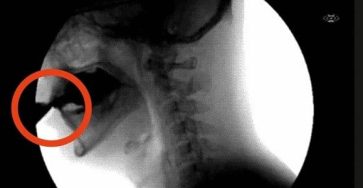

About 15 minutes before a stroke, the body usually sends 4 distinct signals

A stroke is a medical emergency that occurs when blood flow to the brain is interrupted, causing brain damage, disability, or even death. The good news is that the body often sends warning signals up to 15 minutes before a stroke occurs. In this article, we’ll explore four clear warning signs of a stroke, what … Read more